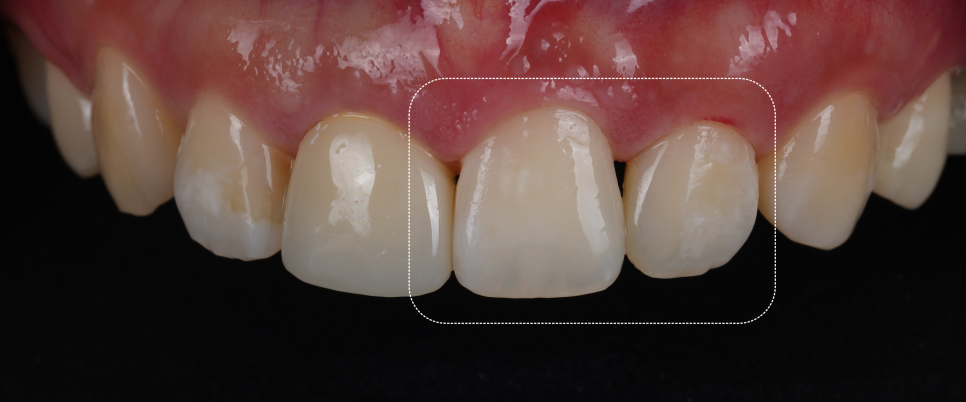

완성 후에는 치아 경계가 사라지고 자연 채광에서 봐도 거친 부분 없이 매끄럽게 보였어요.

촬영일 : 251023

이전의 각진 부분도 사라졌죠.

환자분이 거울을 보시면서 “와.. 진짜 감쪽같아요.” 그 한마디로 피로가 다 풀리더라고요ㅎㅎ

치료 후엔 잇몸과 치아 사이에 아주 얇은 ‘블랙트라이앵글’이 남았는데요.

라고 생각하실 수도 있는데요. 제가 일부로 만들어둔 것이랍니다.

자연스러운 곡선을 살리다 보면 잇몸이 완전히 닿지 않는 부분이 생겨요.

그걸 억지로 메우면 오히려 부자연스러워져요.